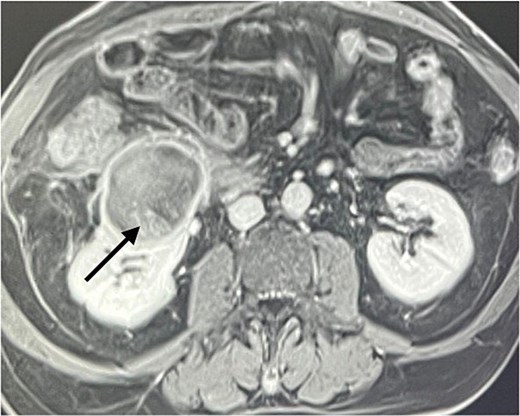

A 60-year-old male patient was referred to our clinic due to concern of infected renal cyst. Five months prior to referral, he underwent an open appendectomy and right limited hemicolectomy due to perforated appendix. At that time he was found to have accidental right Bosniak IIF renal cyst on CT scan and follow up every 6 months was recommended by urologist. Four months later, he came to emergency department with fever, chills and right flank pain. CT scan of the abdomen and pelvis with intravenous contrast was done and showed same size exophytic cyst in the lower portion of the right kidney measuring 4.9 × 5.2 cm but with new finding of rim enhancement with surrounding fat stranding suggesting complicated cyst with possible abscess formation. There was fat stranding and wall thickening of the adjacent ascending colon (Fig. 1). These findings couldn’t differentiate between infected cyst and cancer. Due to the high risk of malignancy associated with Bosniak IIF renal cyst and the challenging differential diagnosis, we further discussed the case with radiologist and decision was made to do an magnetic resonance imaging (MRI) with contrast for further evaluation and for better visualization of internal enhancement. Most MRI findings were suggestive of infected cyst. However, diffusion-weighted imaging and apparent diffusion coefficient (DWI-ADC) map showed strong internal restricted diffusion which is not specific to either abscess or tumor. Reaching the diagnosis based solely on these initial imaging findings was challenging. T1 post contrast image revealed fine internal enhancement suggesting more complex lesion than a simple infected renal cyst or abscess, raising suspicion for a neoplastic process (Figs 2 and 3).

DWI- ADC map shows strong internal restricted diffusion which can present in both abscess as well as tumor (arrow).